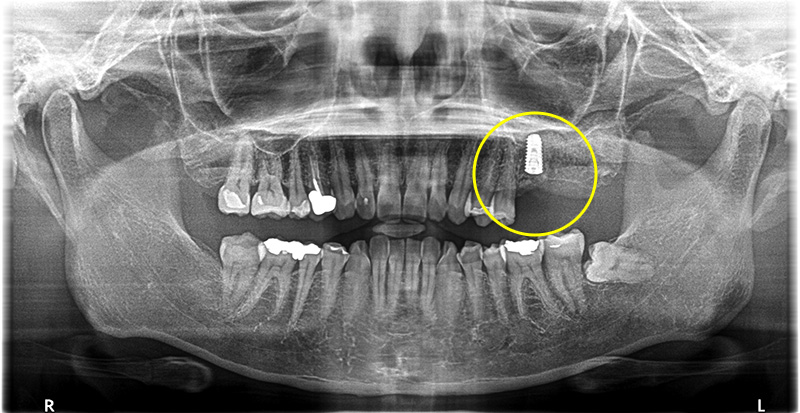

歯根破折のため抜歯しインプラントで修復した症例

こちらの患者さまは、左上6番目の歯が噛むと痛いとの主訴で来院されました。

レントゲンでの検査の結果、歯根に膿がたまっていることがわかり、さらにCTでの検査で、歯根破折が確認できました。

歯根破折により保存不可を説明した結果、抜歯、インプラントでの治療をご希望されました。

骨欠損の範囲が大きく、上顎洞の骨が無くなってしまっていたので、まずは抜歯骨造成のみを行いました。

インプラント治療の実施

5ヶ月し、骨化を確認した後インプラントオペを行いました。